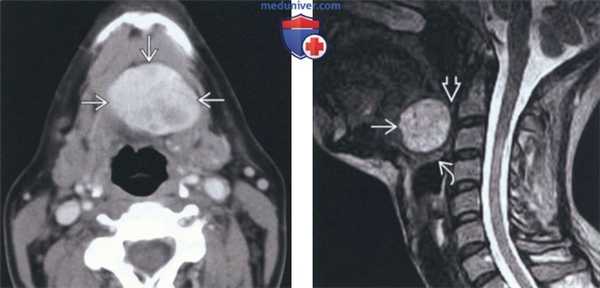

(Слева) КТ с КУ, коронарная проекция. Срединное кистозное образование шеи, которое плотно спаяно с подъязычной костью. У верхнего края кисты имеются плотные кальцификаты и накапливающий контраст мягкотканный компонент.

(Справа) КТ с КУ, сагиттальная реконструкция. Солидное неоднородное образование? расположенное сразу ниже подподъязычной кости, у нижней части которого имеются кальцификаты. Над подъязычной костью визуализируется небольшой дополнительный остаток эктопированной ткани. Щитовидная железа в своем типичном месте отсутствовала.

(Слева) КТ с КУ, аксиальная проекция. Рак щитоязычного протока. Кистозное образование располагается парамедиально в подсвязочном отделе, прорастая в подподъязычные мышцы. Кистозный компонент расположен под слизистой оболочкой подсвязочного отдела гортани. Во внешнем отделе этой кистозной опухоли определяется накапливающий контраст узел, в толще которого имеются кальцификаты.

(Справа) МРТ Т2ВИ в сагиттальной проекции. Кистозное образование, расположенное ниже подъязычной кости. Расположенный выше солидный узел имеет сигнал от промежуточного до низкого. Этот узел, накапливающий контраст, оказался карциномой щитоязычного протока.